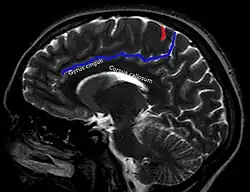

In der Computertomographie und Magnetresonanztomographie ist für die korrekte Lokalisation eines Befundes eine sichere Identifikation des Sulcus centralis oft einer der ersten Schritte. Hierfür haben sich in Abhängigkeit von der Schnittebene verschiedene Strategien etabliert.[4] Beispiele:

Axial Sagittal

1. Im paramedianen Schnitt: Corpus callosum

2. Darüber Gyrus cinguli

3. Darüber Sulcus cinguli (blau) mit

4. Ramus marginalis bis zur Mantelkante

5. Davor Gyrus postcentralis

6. Davor Sulcus centralis (rot)